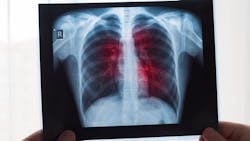

One way to mitigate such problems is to accurately predict the prognosis of patients who test positive for COVID-19. Doctors generally use chest X-ray radiography (CXR) images to assess the condition of patients. By analyzing signs of pneumonia in these images, they can infer if the patient is likely to need admission to the ICU soon. In turn, this can help with optimal allocation of hospital resources. Unfortunately, this process is labor intensive, time consuming, and suffers from variability in diagnoses, which is a major issue especially during large outbreaks.

But what if artificial intelligence (AI) gave us a helping hand? In a recent study published in the Journal of Medical Imaging, a team of researchers from the Department of Radiology of the University of Chicago has developed a deep learning-based model that can predict if a patient will need intensive care by analyzing their CXR images.